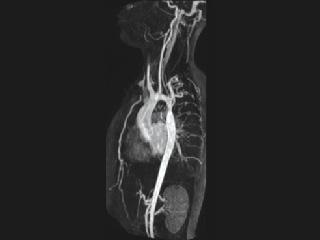

- Coarctation of the Aorta